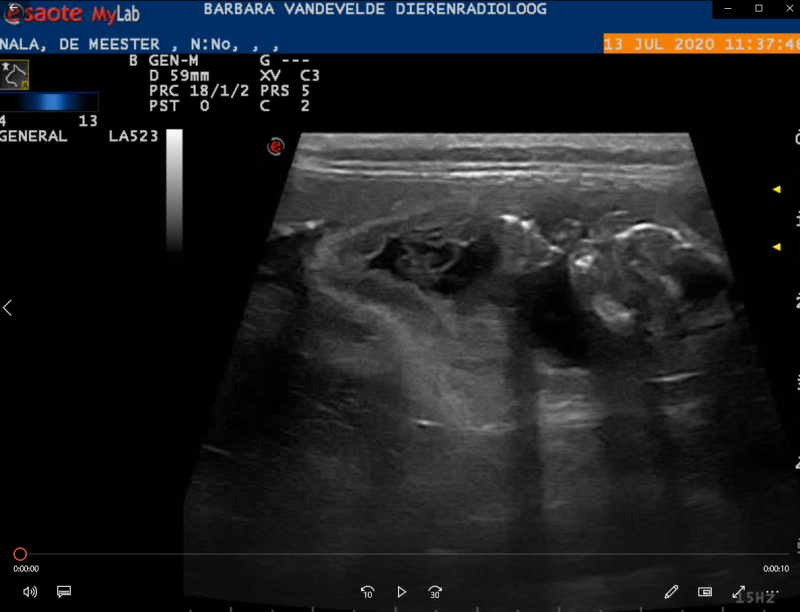

Hoeveel kittens er exact in haar buik zitten is moeilijk te bepalen. We gaan nog een echo laten nemen op 13juli om te zien hoeveel kittens we ongeveer mogen verwachten en of alles in orde met ze is. En dan nog kan er zich altijd eentje verstoppen.😸Dus het definitieve aantal kitten weten we als ze bevallen is.

Bij de radioloog konden we vooral gezonde kittens zien. Het juiste aantal geven we nog niet prijs en kon ook niet meer worden vast gesteld aangezien de kittens al te groot waren. Maar alles was aanwezig en zag er goed uit!